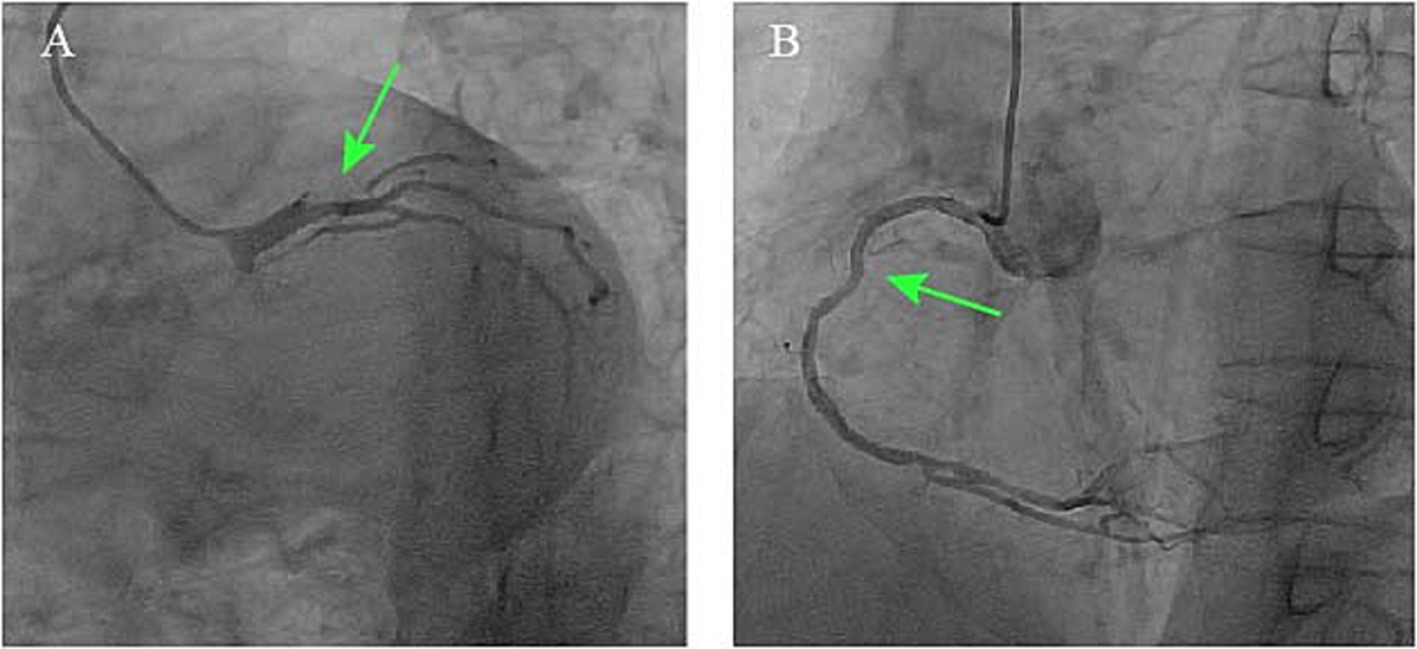

Figure 3

Coronary angiograms demonstrating (A) critical stenosis at the distal left main coronary artery involving the LAD ostio-proximal segment (green arrow) and (B) right coronary artery diffuse disease with Rentrop grade 2 collaterals.

Given the patient’s indeterminate symptom onset timeline, absence of acute anginal symptoms, and hemodynamic stability, guideline-directed medical therapy for heart failure was initiated, comprising antiplatelet therapy, statins, beta-blockers, angiotensin-converting enzyme inhibitors, and mineralocorticoid receptor antagonists. Antibiotic treatment was deferred until completion of the diagnostic workup. After 10 days of medical management, the patient had no significant symptoms of heart failure. A follow-up echocardiogram after 10 days of medical therapy showed persistent severe left ventricular dysfunction (EF 29%) and unchanged valvular abnormalities. Selective coronary angiography demonstrated a critical stenosis at the distal left main coronary artery, specifically involving the ostio-proximal segment of the LAD artery with diffuse disease involving the right coronary artery. Notably, grade 2 intercoronary collateral circulation (Rentrop classification) was observed between the right and left coronary systems (Figure 3). To further evaluate systemic atherosclerotic burden, a carotid artery ultrasound was performed, revealing a normal intima-media thickness (CIMT) of 0.7 mm bilaterally, with no evidence of plaque formation.